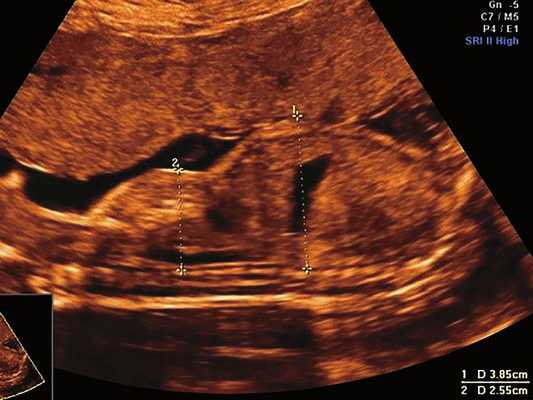

б) Узкая грудная клетка.

в) Изогнутая и укороченная бедренная кость.

г) Изогнутая и укороченная бедренная кость.

| Набл. 1. 24,3 нед. | БПР - 25,3 нед. ОГ - 24,6 нед. Аномально повышенная бороздчатость и выпуклость извилин нижнемедиальной поверхности височных долей (рис. 1а). | Торакоабдоминальное соотношение - 66,7% (рис. 1б) Длина ребра - среднее для 16 нед. | Бедренная кость 19,6 мм (47,8% от должной), изогнута ("телефонная трубка") (рис. 1в). Остальные кости - среднее для 15 нед. | Уплощенные тела поясничных позвонков. |

| Набл. 2. 20,3 нед. | БПР - 21,5 нед. ОГ - 20,3 нед. Уплощенный затылок. Выпуклые темпоральные бугры (рис. 2а). Аномально повышенная бороздчатость и выпуклость извилин нижнемедиальной поверхности височных долей (рис. 2б). | Торакоабдоминальное соотношение - 63,3% (рис. 2в) Окружность груди - среднее для 18 нед. Длина ребра - среднее для 15 нед. | Бедренная кость 17,7% (61% от должной), изогнута ("телефонная трубка") (рис. 2г). Остальные кости - среднее для 13-14 нед. | Гипоплазия костей носа. |

| Набл. 3. 24 нед. | БПР - 30 нед. ОГ - 27,2 нед. Уплощенный затылок. Выпуклые темпоральные бугры (рис. 3а). Аномально повышенная бороздчатость и выпуклость извилин нижнемедиальной поверхности височных долей (рис. 3б). | Торакоабдоминальное соотношение - 56,6% (рис. 3в) Окружность груди - среднее для 20 нед. Сердце/грудь (см 2 ) - индекс 0,6. | Бедренная кость 23,1 мм (57% от должной), изогнута ("телефонная трубка") (рис. 3г) Остальные кости - 50% для 15-16 нед. Нормальная установка пальцев кисти (рис. 3д). | Многоводие. |